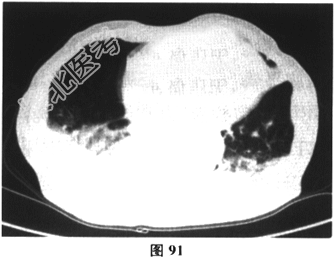

- 多项选择题3.[提示]动脉血气分析:pH7.32, PCO280mmHg,PO250mmHg, SaO285%,HCO-334mmol/L。胸部HRCT结果如图90和图91所示。